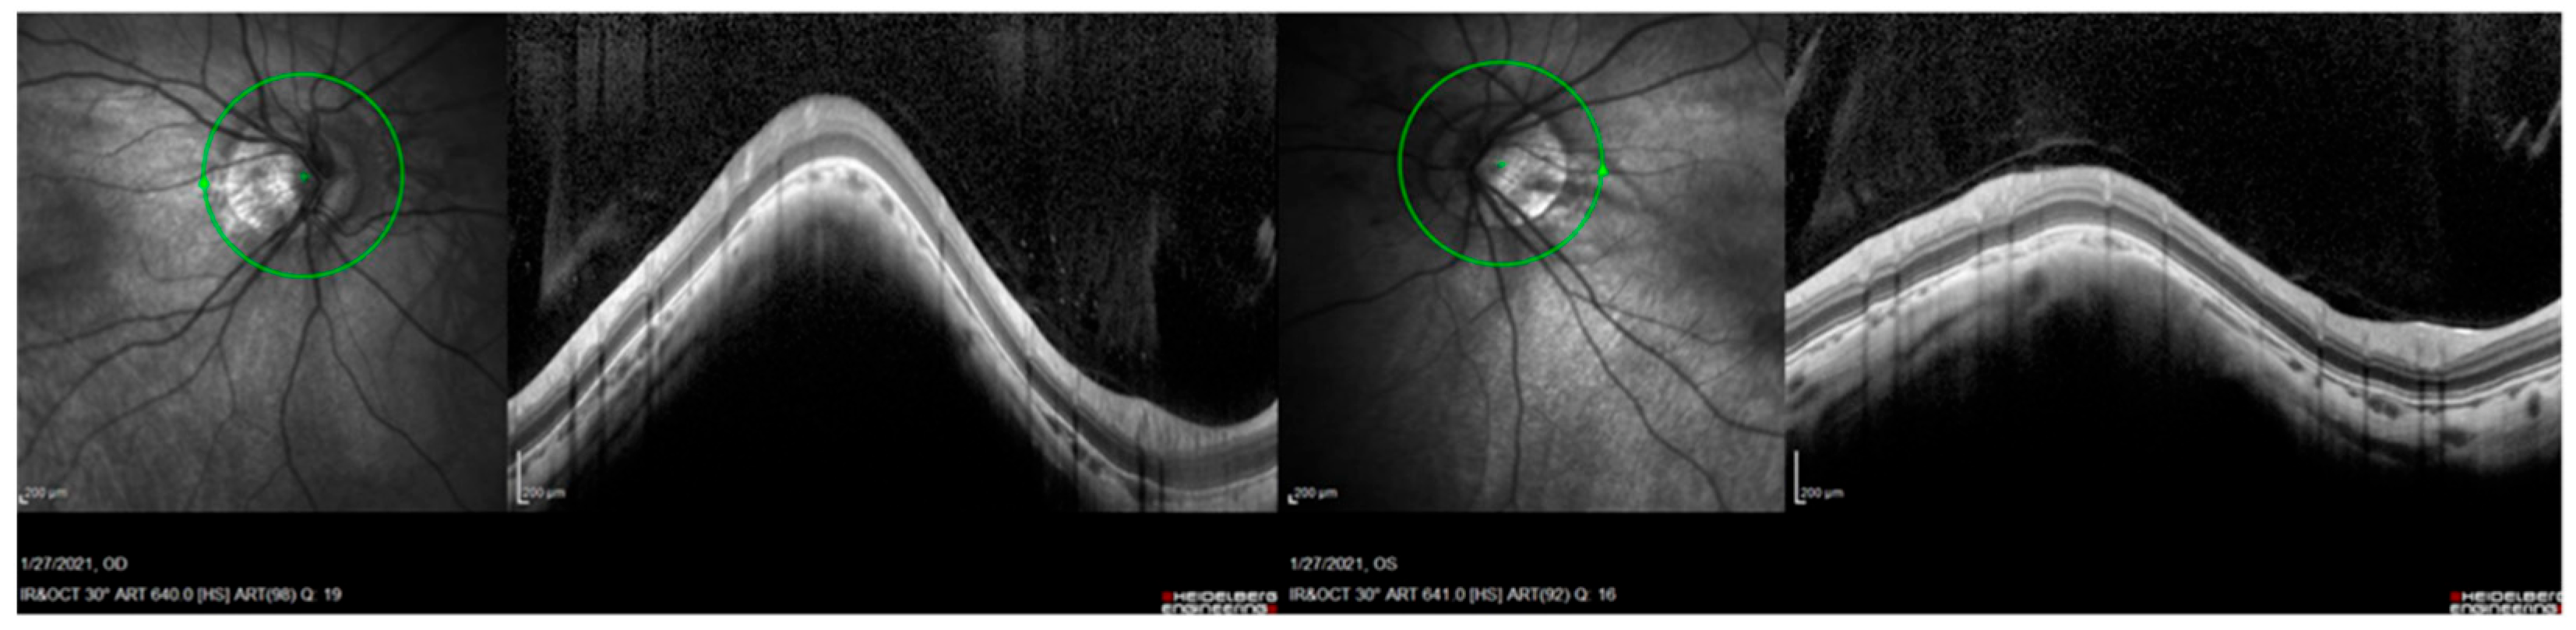

| OFT-00223 | F | 0.3 | 0.3 | 28.04 | 27.62 | Atrophic optic nerve | Atrophic optic nerve | −13.5 | −2.5 | −14.75 | −13 | −0.5 | −13.25 |

| OFT-00343 | EoHM | - | OPA1 | NM_130837.3 | c.1294G>A: p.Val432Ile | PM1, PM2, PP2, PP3, PP5 | LP | Missense | Hetero | AD | Yes | Paternal | Stewart et al., 2008 [32]; Yu-Wai-Man et al., 2011 [33] |